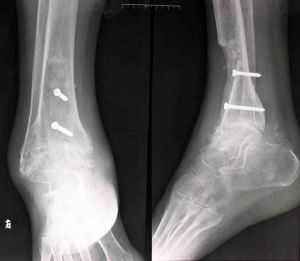

2.X線檢查

X線變化在感染後3~4周出現,表現為骨質不規則增厚和硬化,有殘留的骨吸收區或空洞,其中可有大小不等的死骨,有時看不到骨髓腔。小骨腔和小死骨在硬化骨中有的不能顯影,所以實際存在的數目往往比照片上所顯示的多。

若X線表現不明確,可行CT檢查以確定病變骨及顯示椎旁膿腫的形成,放射骨掃描在病變早期即有反映,但無法區別感染。